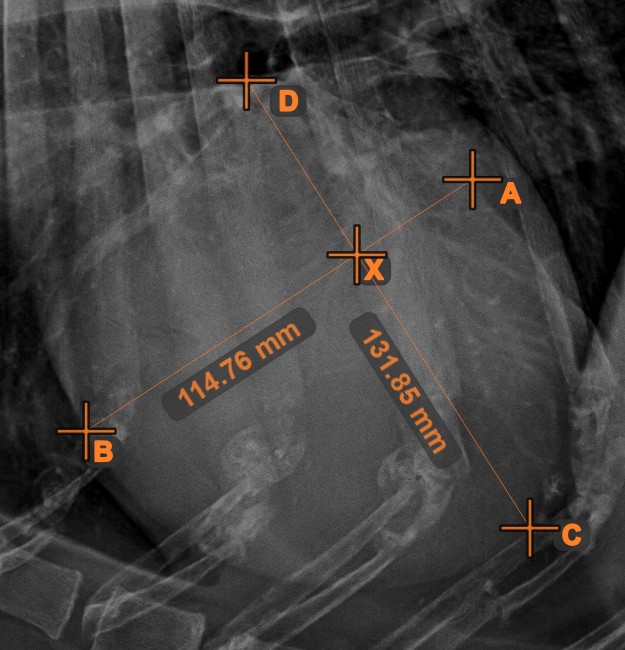

Line Intersection

Quickly and accurately locate and mark the intersection point between two existing lines by using the Line Intersection tool.

Select the tool from the left toolbar and assign it to one of the available mouse buttons. Select two lines that have already been drawn on the scene to complete the measurement. The intersection point of the line will be automatically calculated and marked on the scene. The intersection point of two lines will always be marked with the letter X.

Information

If two lines do not intersect directly, the intersection point of their extended projections on the scene will be marked.

../_images/image408.jpg ../_images/image37.jpg